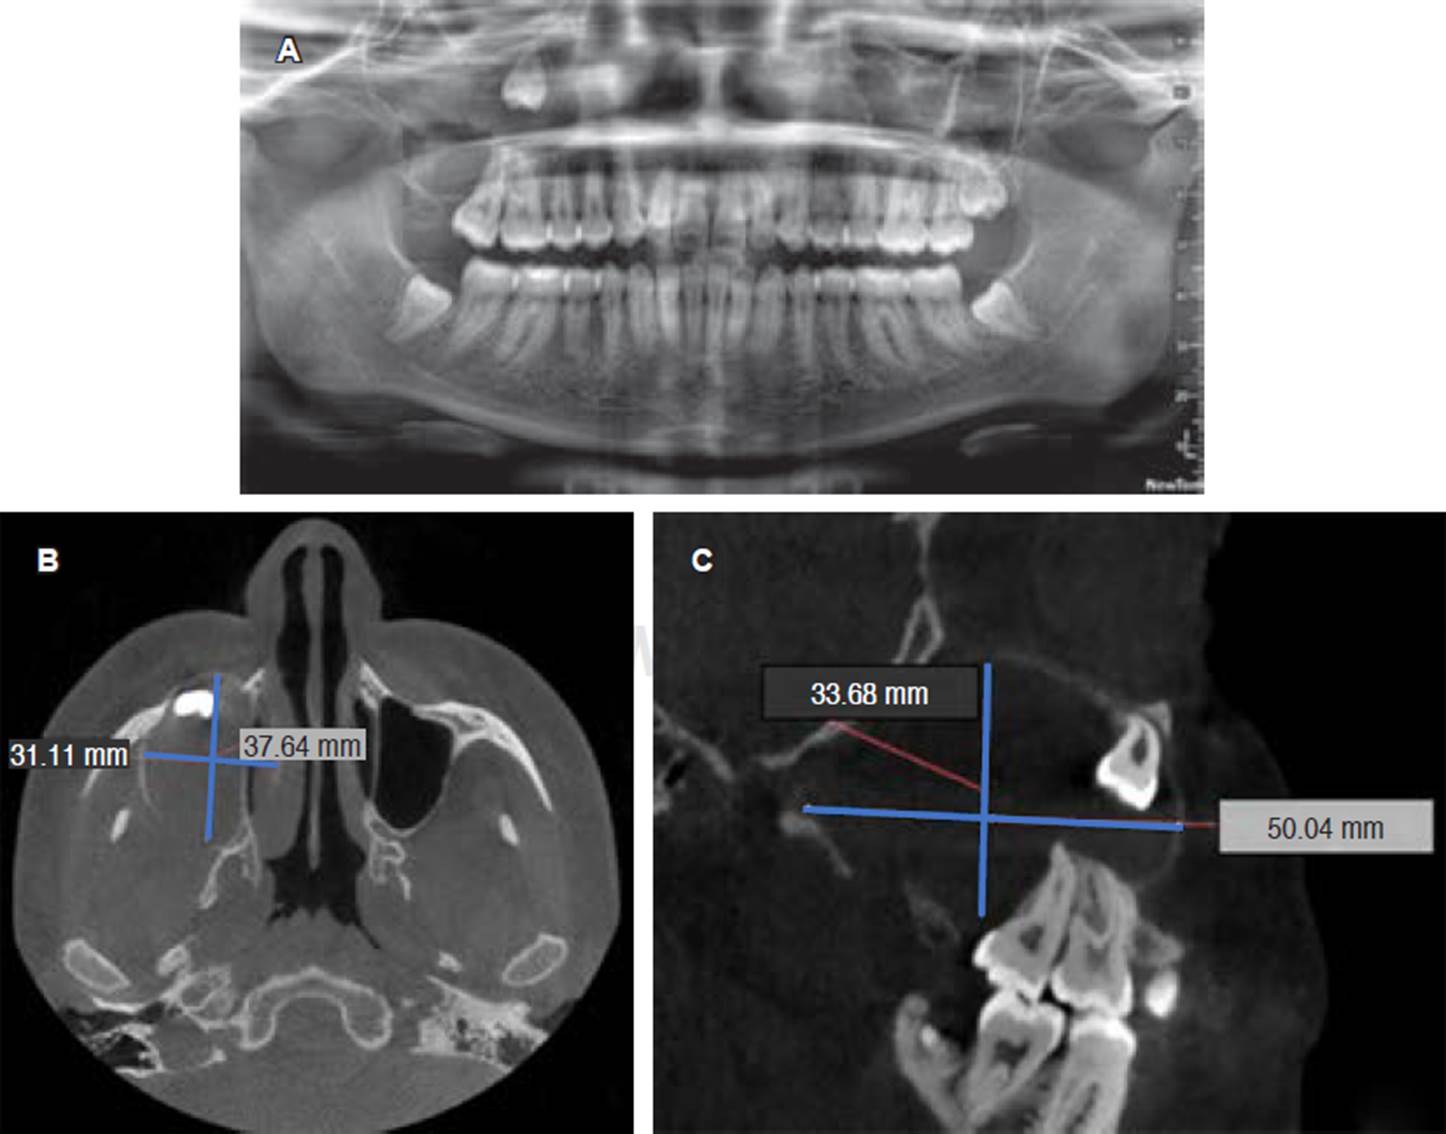

Se presentó paciente femenino de 19 años de edad a la Clínica de Cirugía Oral y Maxilofacial, de la División de Estudios de Postgrado e Investigación (DEPeI) de la UNAM, para la extracción de sus terceros molares; sin antecedentes de importancia para su tratamiento. En la ortopantomografía se observa el tercer molar superior derecho (OD 18) desplazado hasta piso de órbita ipsilateral, con una zona radiolúcida asociada a la corona del mismo, la cual ocupa todo el seno maxilar y se ex tiende hasta la tuberosidad del mismo lado, midiendo aproximadamente 3.3 x 5 cm, mientras que en la tomografía (cone beam) se observó la estrecha relación en tre el ápice del tercer molar con el piso de órbita (Figura 1). Se inició con una punción exploratoria y se observa contenido amarillento compatible con queratina. Luego, se realizó biopsia incisional de la lesión y se extrajo el tercer molar en relación para estudio histopatológico. Se colocó drenaje utilizando una sonda Foley No. 18 y se indicó higiene estricta del mismo (Figura 2).

Figura 1 A) Ortopantomografía inicial en la cual se puede observar lesión asociada a OD 18. B) Corte axial de tomografía cone beam. C) Reconstrucción sagital de tomografía cone beam en la cual se observa relación de OD 18 con piso de órbita y lesión hipodensa asociada a corona dental del mismo.